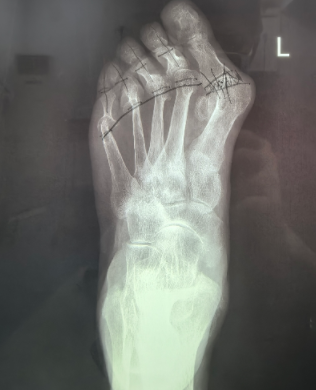

在应对复杂足部健康需求时,年轮医院医疗团队通常会采用多学科协作的模式,充分考虑个体的整体健康状况。例如以王阿姨例,30 年前即出现双足拇指外翻畸形,行走及运动后疼痛显著,经门诊检查确诊为 “双足跖趾关节病”,且患有类风湿性疾病。面对患者年龄大、病程长、合并症多的复杂情况,以闫超主任领衔的团队并未简单套用常规方案,而是通过多学科会诊反复研讨,zui终确定"单足多趾截骨矫形术",针对王阿姨单足 5 个脚趾共计 9 处截骨矫正手术,开展了精准的截骨矫形手术,以精细化操作攻克手术难题。此次手术的成功实施,不仅有效改善了王阿姨的足部畸形与疼痛症状,也体现了我院骨科在复杂足部矫形手术领域的专业技术实力。